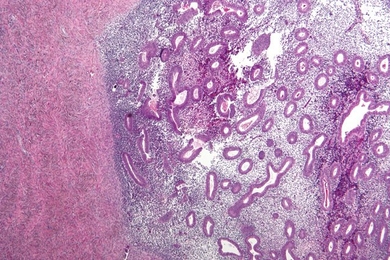

Boston Globe reporter Carolyn Johnson examines a study led by MIT bioengineer Linda Griffith. The study is a first step in providing a more informed way of classifying endometriosis a disease which Griffith herself suffers from.